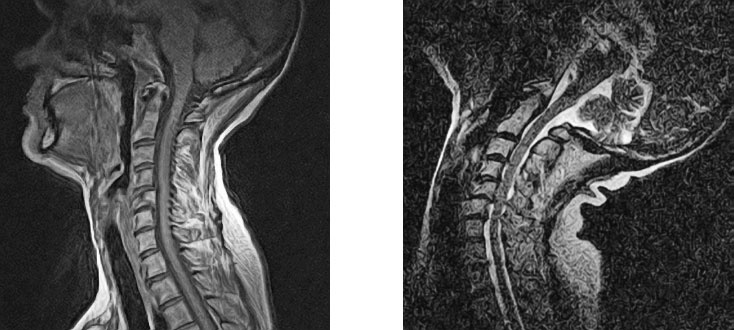

Иллюстрация к книге — Йога при остеопорозе [_27.jpg]

Рисунок 24. Несмотря на разные школы, разные десятилетия, разные континенты, разный пол и разный по продолжительности опыт занятий йогой, здесь мы не видим значительных различий в положении поясничных позвонков.